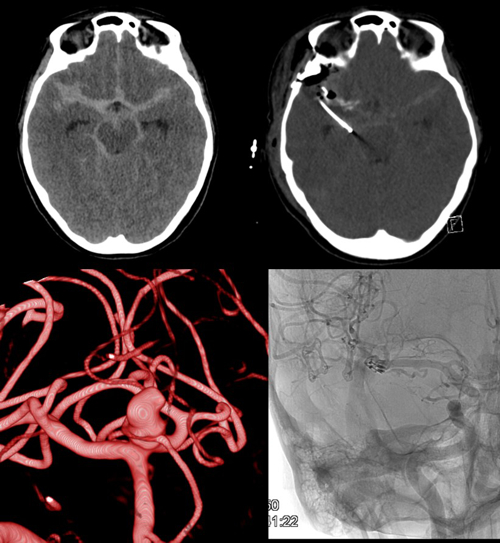

Severe head injury and aneurysmal SAH (Fig. 4) as well as haemorrhagic strokes are common medical conditions in the department. As well as multimodal monitoring and numerous pathophysiological investigations, various multi and monocentric studies are regularly undertaken. Invasive multimodal neuromonitoring of brain oxygenation, metabolism, blood flow and intracranial pressure alongside advanced imaging and targeted metabolomic profiling are performed for continuous evaluation of these techniques in treatment optimisation and patient outcome after subarachnoid haemorrhage and severe/moderate head trauma.